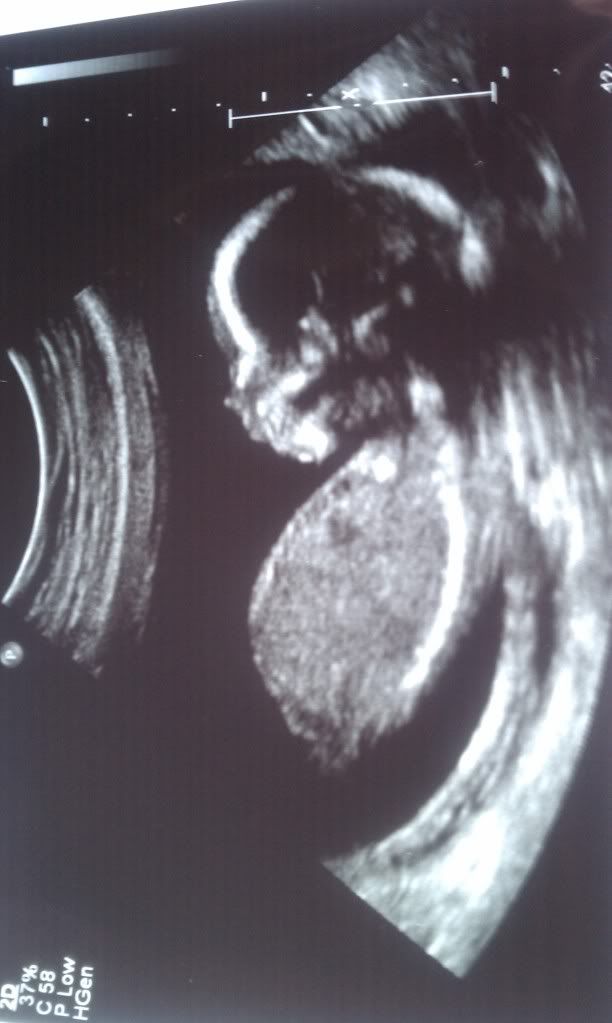

Here is Alexis Renee (on 29 Aug). She has Mommy's belly. LOL